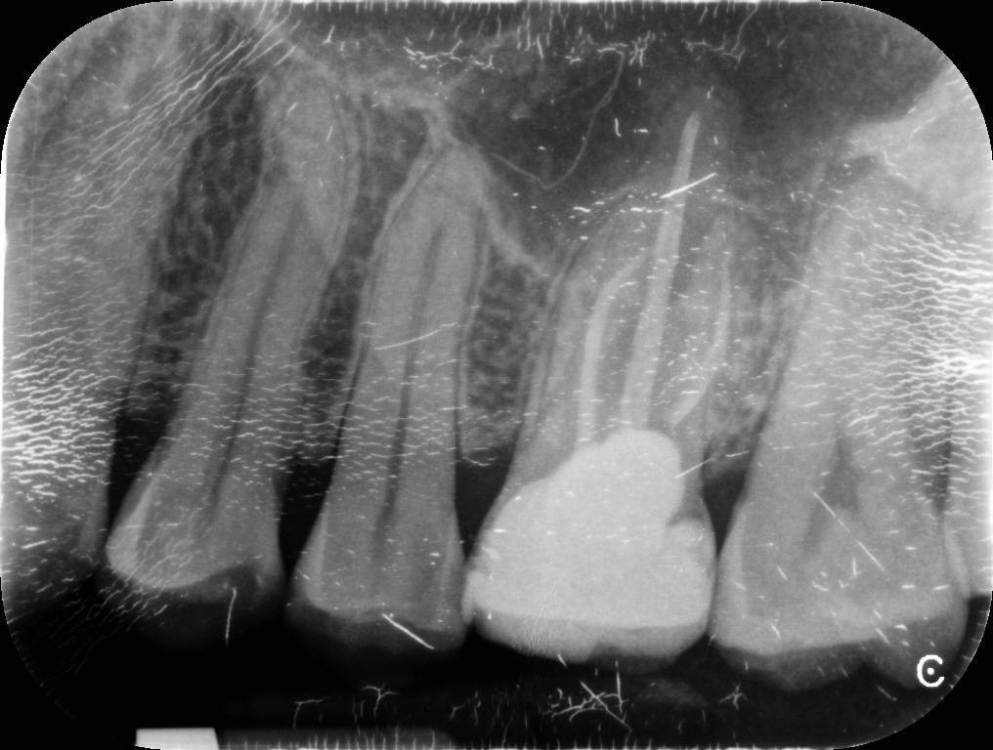

randomsctions Опубликовано 22 апреля, 2023 Автор Поделиться Опубликовано 22 апреля, 2023 Стучали все три врача, но разницы никакой я не заметил. вчера сделали тест: ввели небольшое количество анестетика под каждый зуб с перерывом в 10 мин, чтобы посмотреть, когда утихнет боль. идентифицировали вот этот зуб таким оьразом (оьвёл красным на картинке). Удалили нерв и запломбировали канал. Боль изменилась, но не прошла. Накатывает волнами теперь от почти 0 до 7 по 10-бальной шкале, с периодом около 30 мин +-. Но хотя бы могу спать теперь. Всё ещё буду рад советам, т.к. до сих пор непонятно, в чем проблема. Ссылка на комментарий

randomsctions Опубликовано 24 апреля, 2023 Автор Поделиться Опубликовано 24 апреля, 2023 Добрый день! Наконец-то уговорил врачей сделать КТ. При постукивании, если внимательно прислушиваться, выделяется нижний зуб (обвел красным), ну и верхний депульпированный. Дантист быстро показала КТ эндодонтисту, оба врача ничего страшного там не увидели. Боль продолжается, в состоянии покоя снижается до 1-2, после еды или воды возрастает до 7-8, потом плавно возвращается к 1-2. 741021604_AndreiTiupovCBTCscan.dcm Ссылка на комментарий

Carioznik Опубликовано 25 апреля, 2023 Поделиться Опубликовано 25 апреля, 2023 (изменено) 22.04.2023 в 18:08, randomsctions сказал: Удалили нерв и запломбировали канал сейчас там временная пломба? Судя по КТ - каналы не до конца сделаны. (от этого могут сохраняться боли) На зубе 26 (верхний с большой пломбой) - приличный очаг воспаления из-за пропущенного, когда-то при лечении зуба, канала. Каналы в нём перелечить можно , но есть вопрос с восстановлением и дальнейшим прогнозом (от зуба скорее всего ничего не останется и восстановить его уже не получится нормально , соответственно есть вероятность удаления зуба) 18 часов назад, randomsctions сказал: При постукивании, если внимательно прислушиваться, выделяется нижний зуб Возможно есть рецидив кариеса под пломбой , но это только предположение, нужен очный осмотр. (вряд-ли он причина ваших проблем, но я бы взял его на заметку) еще бы верхний предпоследний более детально посмотреть (очно и доп.прицельный снимок) пока вывод такой: долечить зуб , где удалили нерв. Далее переходить к верхнему зубу с большой пломбой. PS сделайте хоть фотографию во рту, если получится. может что-то еще прояснится Изменено 25 апреля, 2023 пользователем Carioznik 1 Ссылка на комментарий

randomsctions Опубликовано 28 апреля, 2023 Автор Поделиться Опубликовано 28 апреля, 2023 Большое спасибо за ответы! Мне удалось найти хорошего врача, который смог своим умом предложить то же самое, о чем мне писали в этой теме. 25.04.2023 в 04:25, Carioznik сказал: долечить зуб , где удалили нерв. Далее переходить к верхнему зубу с большой пломбой. еще раз спасибо! сейчас именно такой план лечения и наметили. 2 Ссылка на комментарий